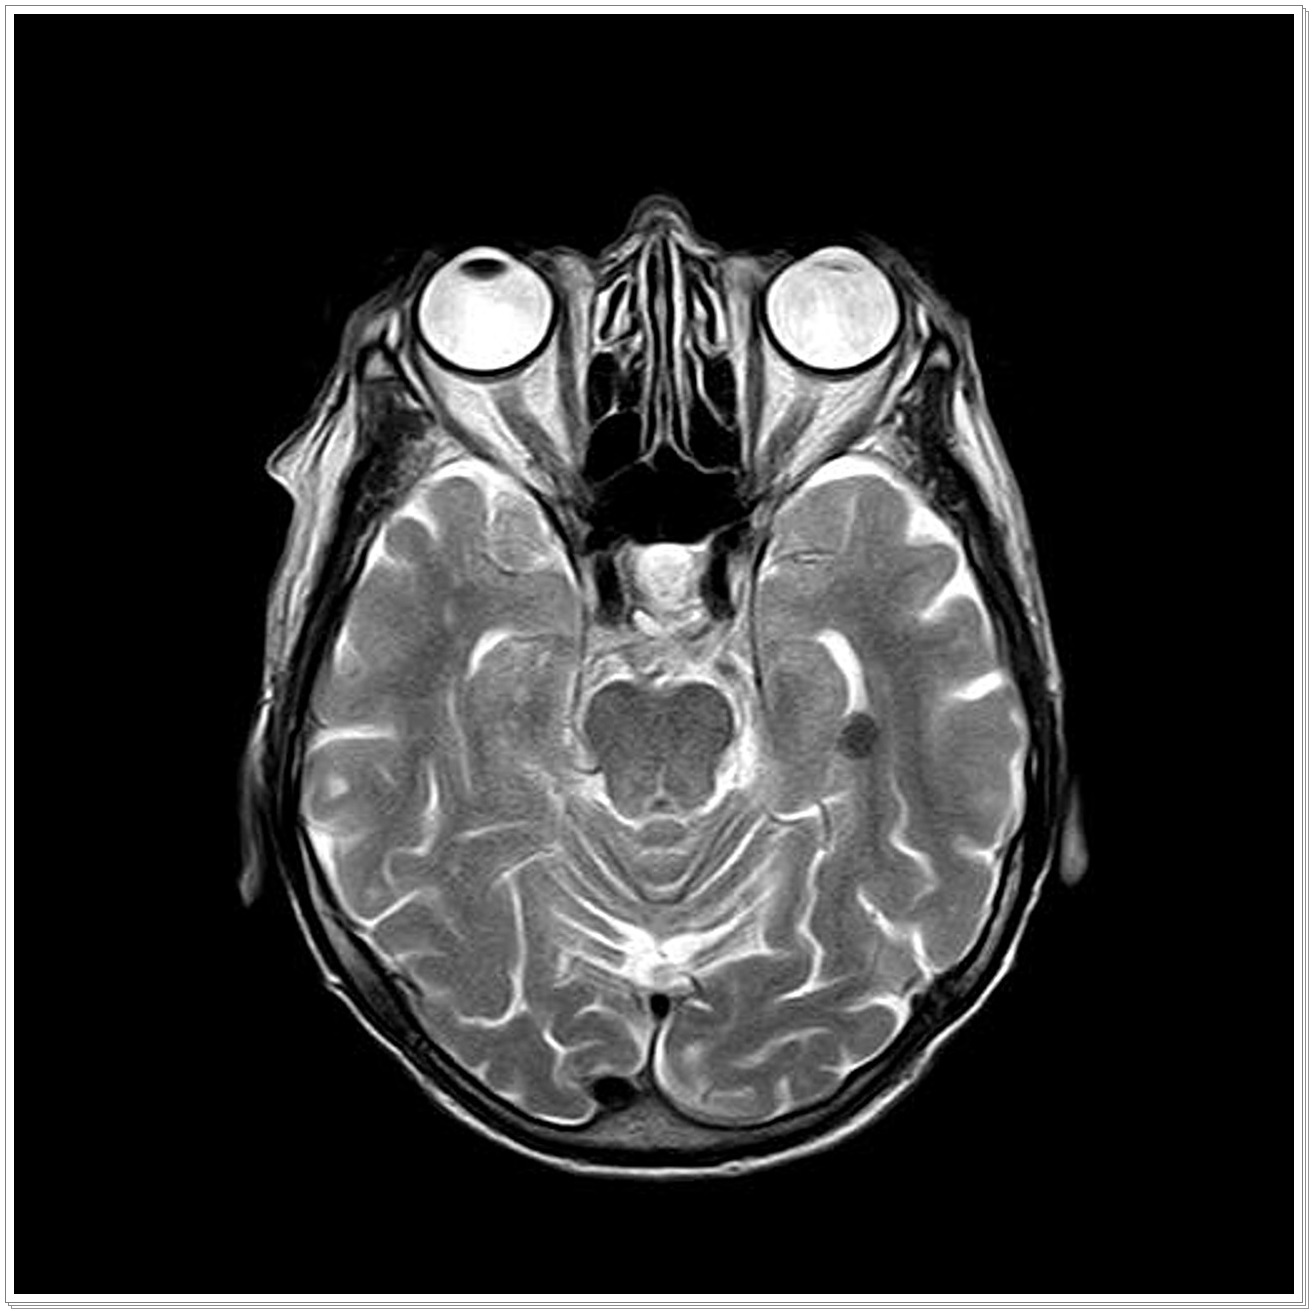

2019년 5월 1일부터는 눈. 코. 귀. 안면 MRI 검사 건강보험 적용하여 검사비 부담이 1/3 수준으로 떨어집니다.

하지만 2019년 5월 1일부터 안면 등 두경부 MRI검사의 건강보험 적용이 확대되었습니다.

▷ 의사가 MRI 검사를 통한 정밀 진단이 필요하다고 판단하는 경우 건강보험이 적용.